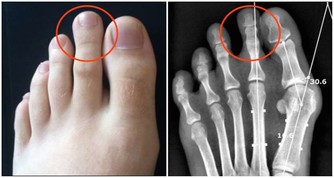

對於人體來說,這部分營養無法被消化,也無法被利用,但這並不意味著它們沒用。這時身體內的不法分子,如潛在的腫瘤因子等就會接收這些“廢物”,供自己享用,一旦時機成熟就會變成令人談之色變的腫瘤。